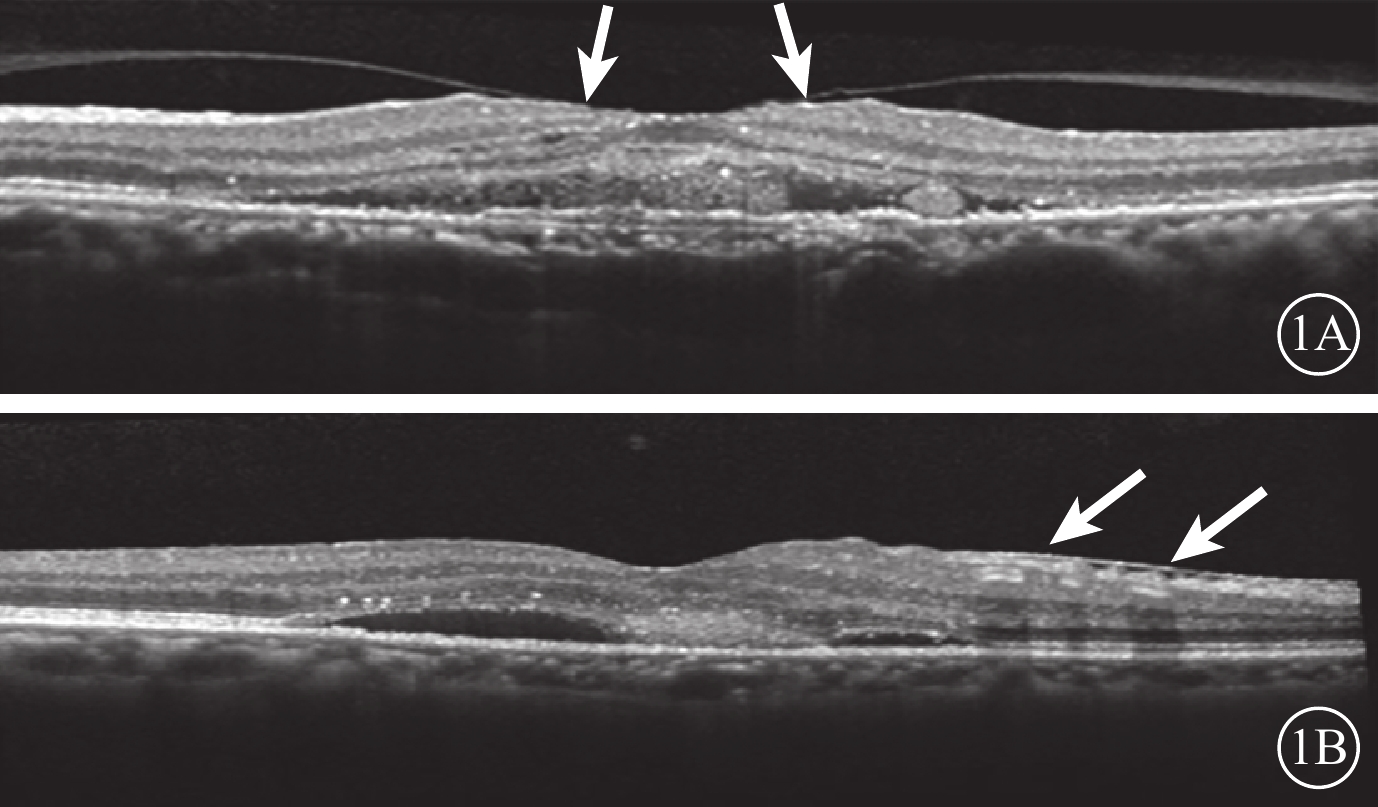

末次隨訪時,34只研究眼中,VMI異常12只眼。其中,廣泛型VMA 5只眼,局灶型VMA 2只眼,C-PVD 3只眼,MEM 2只眼;合并存在C-PVD、MEM 1只眼。與治療前比較,共有6只眼VMI發生變化(圖3)。34只對照眼中,VMI異常13只眼。其中,廣泛型VMA 5只眼,C-PVD 7只眼,MEM 1只眼。與治療前比較,共有6只眼VMI發生變化(圖4)。治療前研究眼中局灶型VMA 3只眼,其末次隨訪時發生C-PVD 2只眼。治療前對照眼中局灶型VMA 2只眼,末次隨訪時均發生C-PVD(表1)。

末次隨訪時,34只研究眼中,VMI異常12只眼。其中,廣泛型VMA 5只眼,局灶型VMA 2只眼,C-PVD 3只眼,MEM 2只眼;合并存在C-PVD、MEM 1只眼。與治療前比較,共有6只眼VMI發生變化(圖3)。34只對照眼中,VMI異常13只眼。其中,廣泛型VMA 5只眼,C-PVD 7只眼,MEM 1只眼。與治療前比較,共有6只眼VMI發生變化(圖4)。治療前研究眼中局灶型VMA 3只眼,其末次隨訪時發生C-PVD 2只眼。治療前對照眼中局灶型VMA 2只眼,末次隨訪時均發生C-PVD(表1)。